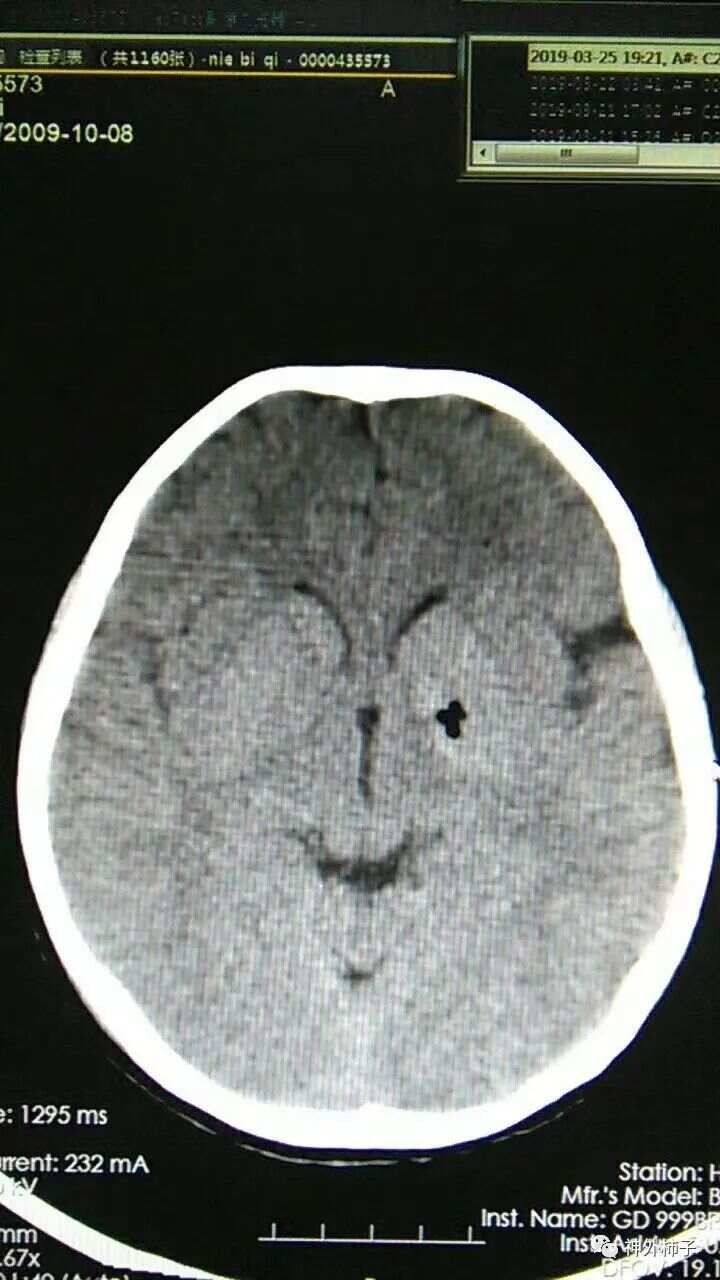

术后复查头颅CT,左侧基底节区病灶已经取出,未见出血。